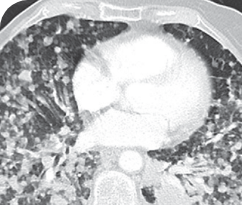

INITIAL DIAGNOSIS

6 WEEKS AFTER TREATMENT

30-YEAR-OLD FEMALE WITH BONE METASTASES2

PATIENT CASE:

METASTATIC NSCLC1,a

- 30-year-old female

- Progression on first-line doublet chemotherapy

- PRa after 6 weeks of treatment with VITRAKVI® (larotrectinib)

- Complete clinical response achieved by 12 months with residual scarring

Clinical presentation1

- Nonsmoker and a history of atopic eczema

- Presented with dyspnea and pleural effusion

- Bone-scan imaging revealed 3 metastatic lesions of the pelvis, in the sacrum, acetabulum, and ischial bones, which were asymptomatic

- Diagnosed with metastatic adenocarcinoma of the right lung in March 2017

VITRAKVI treatment1

- VITRAKVI 100 mg twice daily orally

Response to VITRAKVI1

- Partial response and symptom improvement confirmed by chest X-rays after <1 month of treatment

- Imaging performed 6 weeks into treatment revealed considerable decrease in the size of both target lesions

- No treatment-related AEsa were reported

- Patient was symptom free and remained on VITRAKVI

Response in primary and metastatic lesions1

Lung imaging of primary tumors.

SCAN 1: LUNG

SCAN 2: LUNG AND BONE

Images courtesy of Dr Maximilian Hochmair.